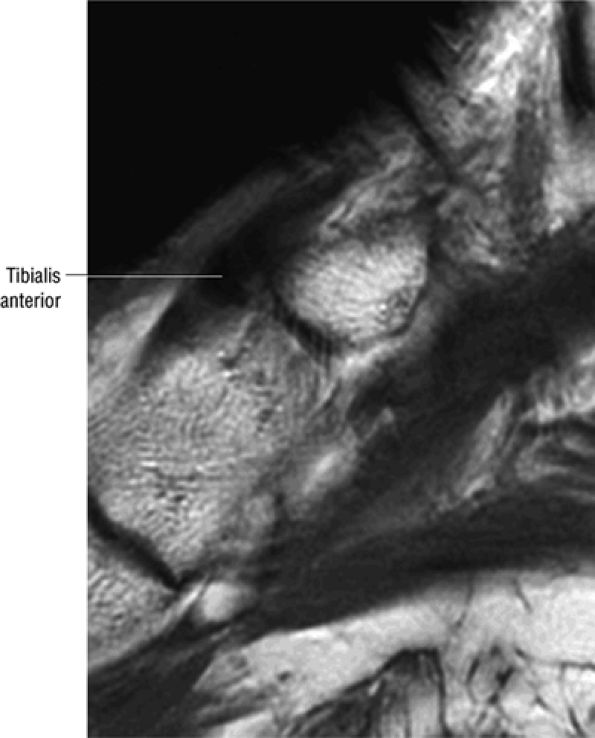

The anterior muscles of the leg are the tibialis anterior (Fig. 5.2), the extensor hallucis longus (Fig. 5.3), the extensor digitorum longus (Fig. 5.4) and the peroneus tertius (Fig. 5.5).

![]() |

|

FIGURE 5.2 ● TIBIALIS ANTERIOR The tibialis anterior muscle functions eccentrically after the heel strike to control deceleration of the foot and concentrically after the toe-off in ankle dorsiflexion. In runners and hikers, paratenonitis is associated with the use of excessive eccentric contraction during midfoot and forefoot impact on downhill slopes. Paratenonitis is also associated with direct mechanical irritation from ski boots or hockey skates. The tibialis anterior dorsiflexes and inverts the foot.

FIGURE 5.3 ● EXTENSOR HALLUCIS LONGUS Extensor hallucis (and extensor digitorum) injuries are similar in origin to injuries of the tibialis anterior tendon. Extensor hallucis longus (EHL) paratenonitis is associated with pain and swelling localized to the ankle joint with painful resisted extension of the hallux. The EHL extends the great toe and dorsiflexes the foot.